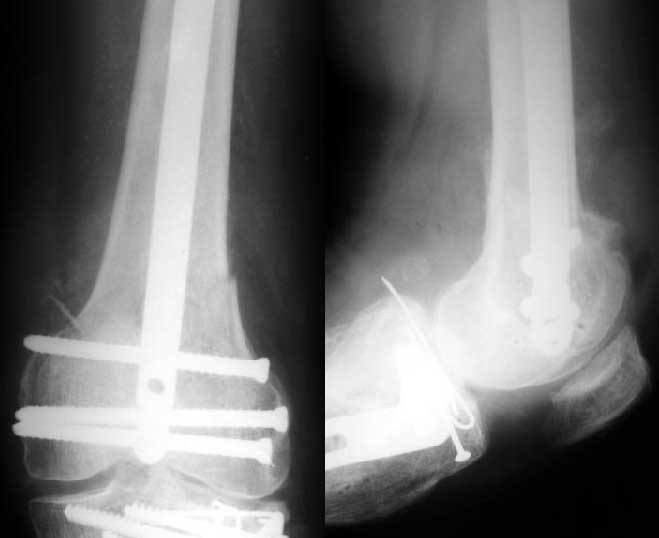

Отправитель: Alexander Chelnokov 27 Декабрь 2003, 21:34

Sorry but I've just prepared postop images - attached. A solid 13 mm nail was used. A few degrees of recurvation appears to be which i missed on image intensifier. I'm still uncertain about

advantages/disadvantages of ante/retrograde nailing for such fractures.

Отправитель: V.M.Iyer 27 Декабрь 2003, 21:36

The fixation as you have done is excellent. The locking screws on either side of the # are so apart. When we put in a supracondylar nail thro a keyhole incison in the knee, the locking bolts will be nearer the # and will be more stable allowing him to bear wt early. That was the reason the supracondylar nail was innovated. The locking is done by jig and no freehand method saving time.